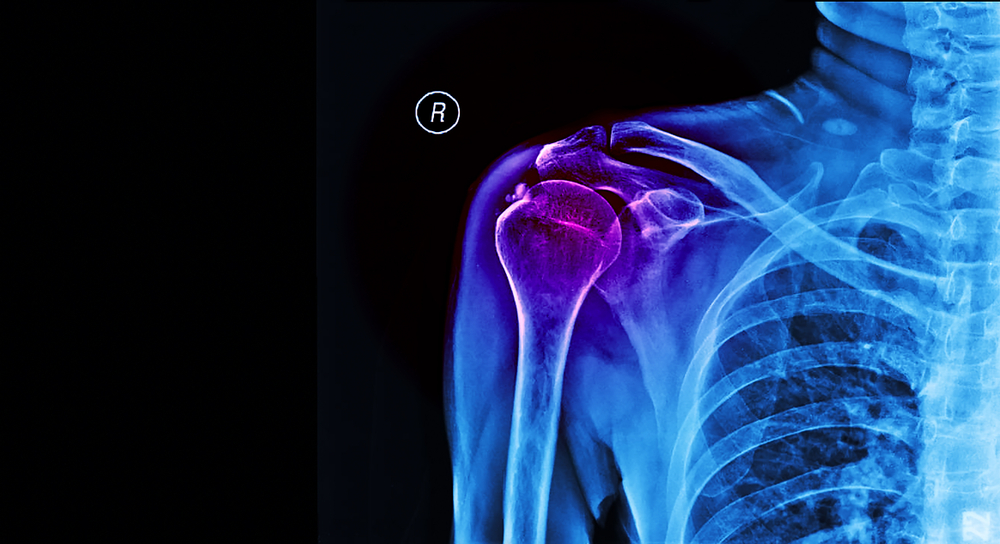

osteoartritis

artritis reumatoidea

tejidos muy dañados o desgarrados en el hombro